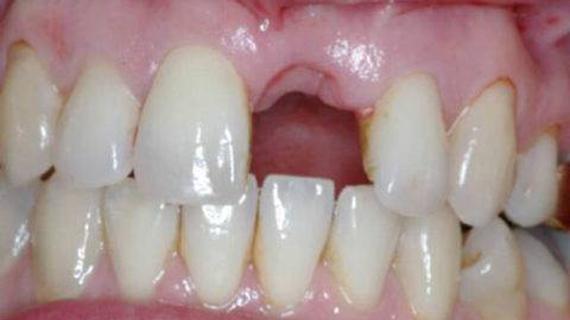

Пульпиты временных зубов в практике детского врача стоматолога: актуальность проблемы, особенности клиники и лечения

Распространенность пульпитов. Временные зубы играют важную роль в жизни растущего организма ребенка. Они оказывают влияние на развитие...